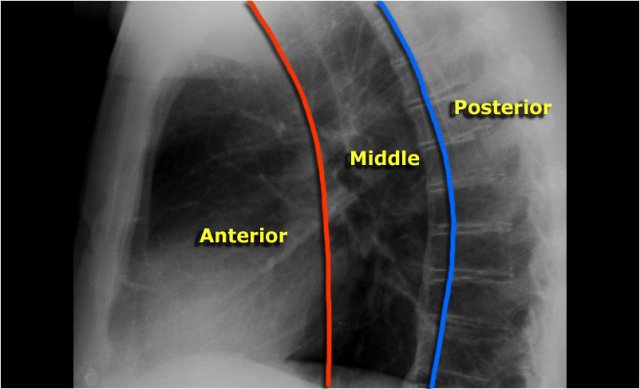

The mediastinum can be divided into an anterior, middle and posterior compartment, each with it's own pathology.